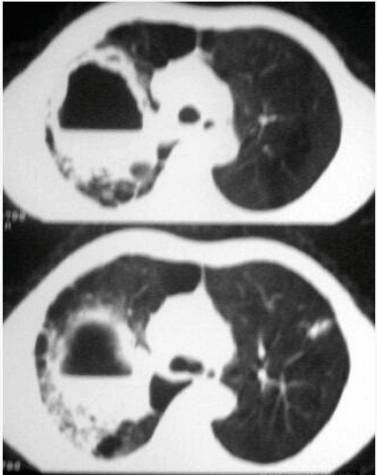

三、肺叶、肺段病变的空洞

肺叶、肺段实变或肺不张可合并空洞,主要为大叶性肺炎、肺脓肿、肺结核和肺癌。

(二)肺结核

1.虫噬状空洞:又称无壁空洞,见于干酪性肺炎及大片纤维干酪灶。一般为单发空洞,可合并支气管又称无壁空洞、干酪空洞,见于干酪性肺炎及大片纤维干酪灶。影像表现为肺叶、肺段或大片实变影呈单发、多发或融合,空洞直径约0.5~1.0cm,类圆形,洞壁模糊

2.硬化多房性空洞:肺结核毁损肺内的空洞为多发性,呈类圆形或不规则状,常紧密相连,洞壁有大量的纤维结缔组织,周围有多种形态及不同密度的结核病灶,如干酪组织、肉芽组织、肺硬变、胸膜增厚等。

3.慢性纤维空洞型肺结核:空洞为纤维厚壁空洞,常为多发性。周围有浸润、干酪结节、纤维化及胸膜增厚等多种病变,肺脏体积减小。